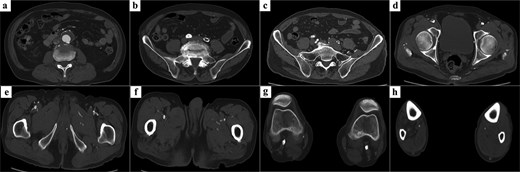

An 83-year-old man with a history of coronary artery bypass grafting, diabetes mellitus, dyslipidemia, and hypertension presented with intermittent claudication of both legs. Eleven years earlier, he had undergone stent placement in the right common and external iliac arteries for AIOD. At this presentation, ankle–brachial indices (ABI) were immeasurable bilaterally. Contrast-enhanced computed tomography (CT) revealed an infrarenal AAA and occlusion of the right external and left common iliac arteries due to severe atherosclerosis and calcification (Fig. 1, Video 1). The bilateral superficial femoral arteries were heavily calcified, and distal runoff was dependent on profunda femoris collaterals. Therefore, surgical planning included open AAA repair with concomitant aorto–bilateral profunda femoris bypass. The right internal iliac artery had favorable quality and was also selected as an additional outflow target.

Preoperative CT findings. (a) A 40-mm infrarenal AAA. (b) Complete occlusion of the left common iliac artery. (c) A patent right internal iliac artery with favorable quality. (d) Occlusion from the right external iliac artery to the common femoral artery because of severe calcification. (e) Occlusion of the right superficial femoral artery and a patent profunda femoris artery serving as the target outflow vessel. (f) A patent left profunda femoris artery. (g) Severe calcification of both popliteal arteries. (h) Distal runoff beyond the tibial trifurcation was maintained via collateral flow from the profunda femoris artery.